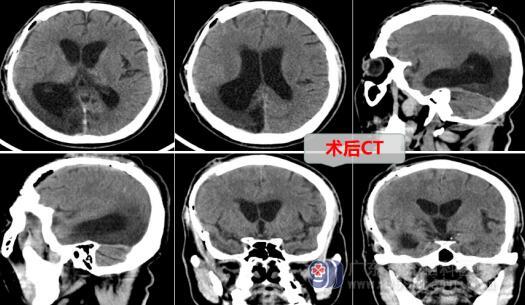

蔡先生家属联系了广东三九脑科医院外十科,欧阳辉主任及其团队对蔡先生制定了手术方案,主管医生向家属讲解手术方式并取得同意。手术当日在全麻下进行了右侧额颞顶颅骨修补术,手术过程顺利,术后切口愈合良好,蔡先生的头颅又恢复了以前的完整性,外形对称、美观。

医生解释,颅骨修补术除解决颅骨缺损外,还对患者伤后造成的脑供血不足、脑脊液循环障碍,以及脑内压不稳定等问题都有一定帮助。一般是在颅骨缺损后3个月后进行,修补条件包括:颅骨缺损部位压力不高、切口无感染、皮肤无溃疡等不利于切口愈合等因素。术后早期观察包括:患者伤口愈合、整形效果及并发症发生情况等,3个月后随访评定疗效。